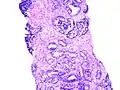

Gleason Grad 5

Gleason Grad 5